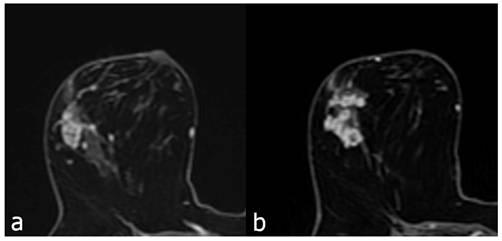

Figure 5

Contrast enhanced breast MRI, linear heterogeneous branching type enhancing NME lesion (a) 56 years old, atypical ductal hyperplasia due to biopsy. Similarly, in a 44-year-old patient with NME lesion showing linear heterogeneous branching contrast enhancement (b), the biopsy result was DCIS.

The 123 cases showing linear distribution were additionally divided into two groups according to whether the contrast enhancement showed branching or not. Of the cases showing linear distribution, 75 did not show branching, while 48 showed branching. Of the cases showing branching, 22 (45.8%) were malignant, and 26 (54.2%) were benign pathologies. Of the cases not branching, 19 (25.4%) were malignant, and 56 (74.6) were benign pathologies (Figure 5). When malignant pathologies were evaluated as DCIS and invasive carcinoma; 16 of the branching group (n=22) were DCIS and 6 were invasive carcinoma. In the non-branching malignant group (n=19), 17 cases were DCIS and 2 cases were invasive carcinoma (Table 5).

The PPV of the non-branching pattern was 25% (19 of 75 lesions; 95% CI: 20-31%). In contrast, the PPV of the branching pattern was 46% (22 of 48 lesions; 95% CI: 40-51%). The PPV of the branching pattern was significantly higher than the PPV of the non-branching pattern (P<0.005).